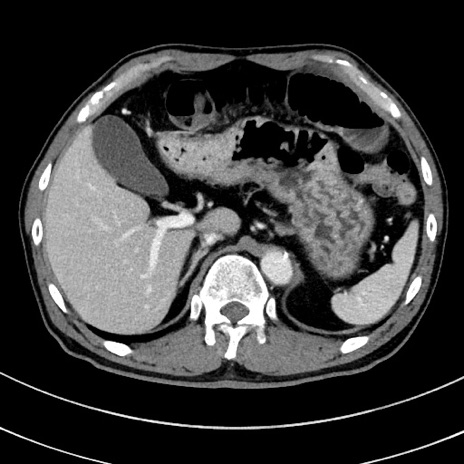

症例8(横断像)

【症例】 60歳代男性

【主訴】 黒色吐物

【現病歴】 4日前から嘔気自覚、2日前の朝食後にも嘔気あり、自分で手で嘔吐反射起こし嘔吐したところ血が混ざっていたため受診。

【既往歴】 5年前汎発性腹膜炎を伴う急性虫垂炎で手術、高血圧、前立腺肥大症、高脂血症

【身体所見】 腹部正中に手術癩痕あり 腹部平坦・軟圧痛なし膨満感あり

【データ】WBC 8400、CRP 4.54